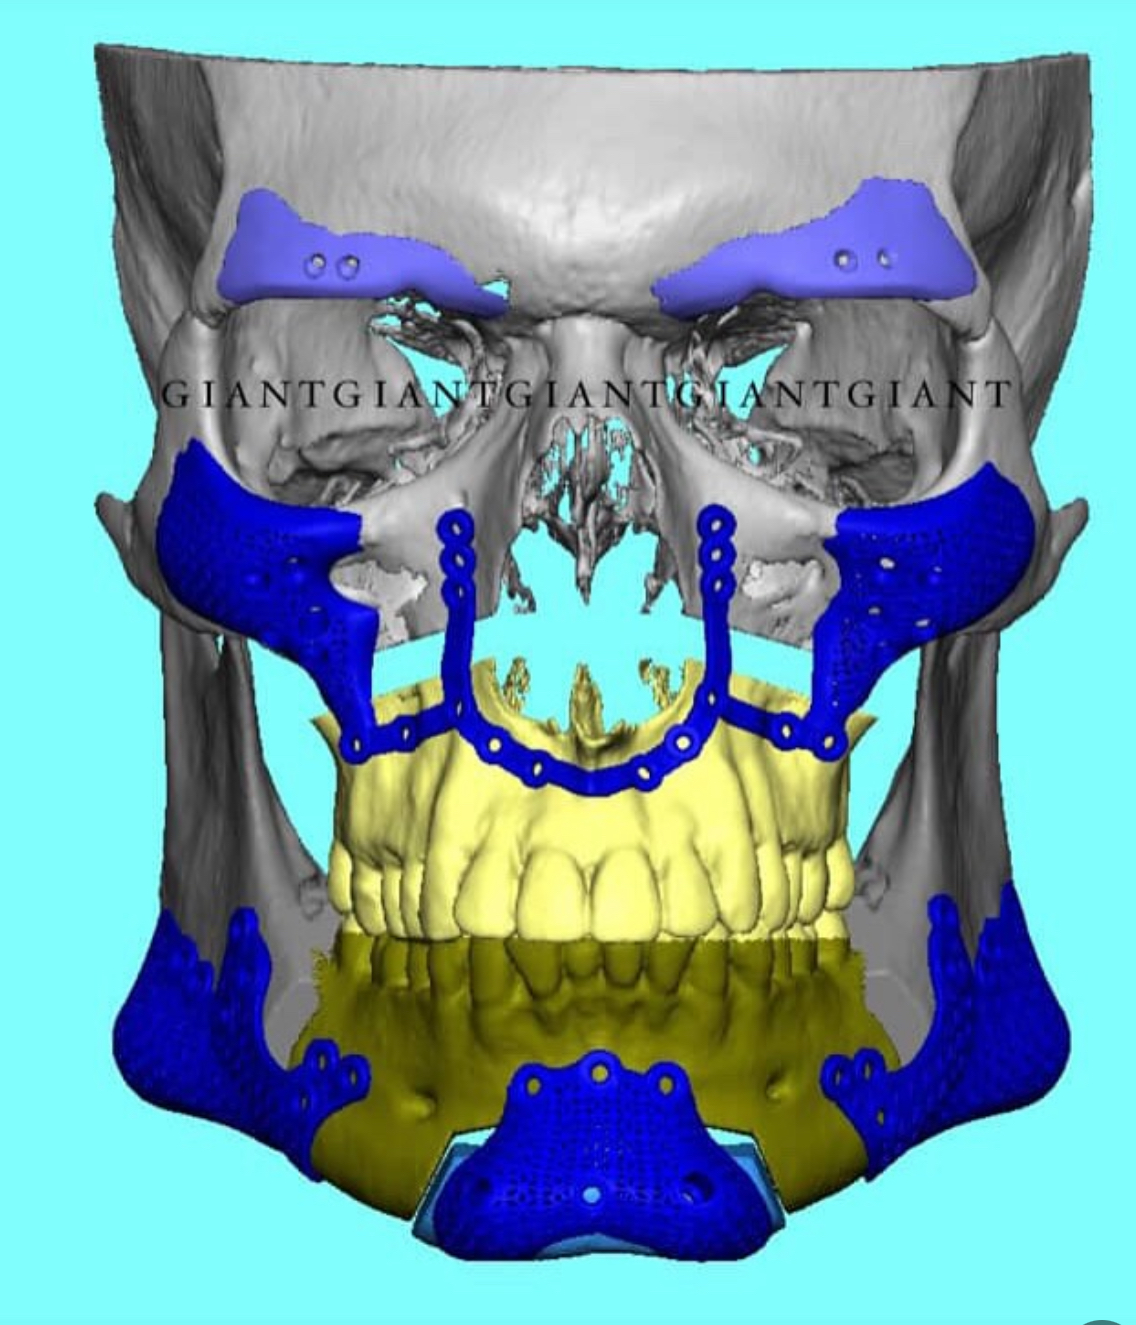

now compare it to Clavicular’s plan for implants designed by GIANT:

I bring this up because compared to Clavicular’s implant design, it is very conservative.

and the thing is: Clavicular’s design, compared to most GIANT designs, is conservative — because Clavicular DOESN’T FUCKING NEED JAW IMPLANTS.

now compare it to Clavicular’s plan for implants designed by GIANT:

I bring this up because compared to Clavicular’s implant design, it is very conservative.

and the thing is: Clavicular’s design, compared to most GIANT designs, is conservative — because Clavicular DOESN’T FUCKING NEED JAW IMPLANTS.